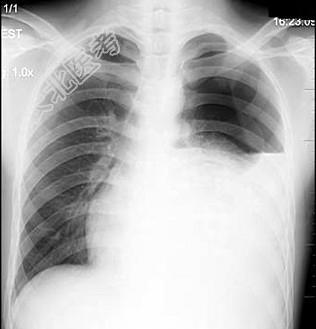

- 单项选择题患者男性,18岁, 感胸闷气逼,胸片检查见图, 最合理的诊断是 ( )

A、左侧胸膜肥厚

B、左侧胸腔积液

C、左侧液气胸

D、左侧肺不张

E、左侧气胸